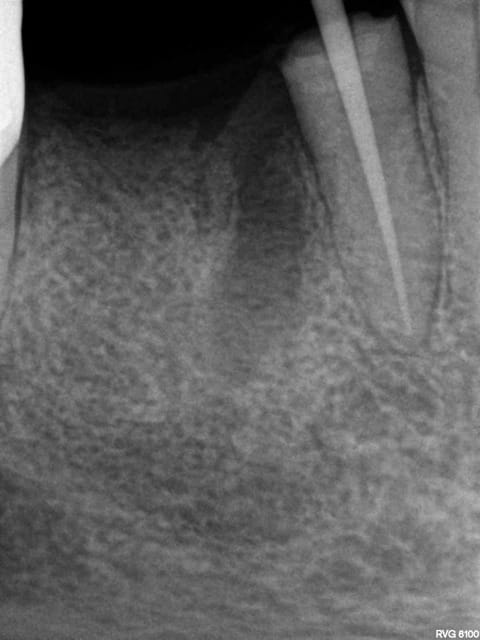

Exemple endo 45 taille empreinte. ( mac spaden) 35 mn.

Radio cone en place, cone scellé, mac spaden, logement tenon.